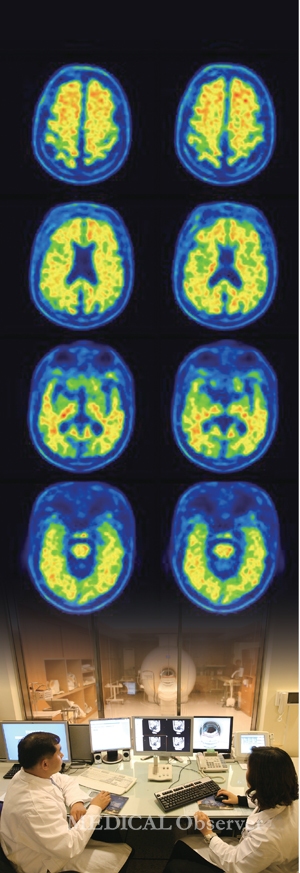

지금까지 다양한 뇌영상기술을 이용한 정신질환 평가 현주소를 통해 뇌영상기술이 임상적 진단 및 치료에 기여할 수 있을지 알아봤다.

현 단계에서 드는 의문은 과연 언제쯤 환자의 병력청취와 임상 증상 평가를 벗어나 영상을 필두로 한 진단이 가능한가에 있다.

이 같은 물음에 연세의대 김재진 교수(세브란스병원 정신건강의학과)는 "현재로써는 뇌영상기술 유용성이 연구 목적에 한정돼 있고, 임상적 가치도 제한적이라서 뇌영상기술을 이용한 진단이 수년 내 가능할 것이라고 단언할 수 없다"고 답했다.

이유는 정신건강질환 진단을 위한 바이오마커가 여전히 불명확하기 때문이다.

김 교수는 "정신건강질환 원인을 밝히는 데 있어 생물학적으로 이상이 있다는 근거는 거의 확실하다. 다만 일관된 진단적 표지자, 즉 바이오마커가 명확하지 않아 진단에 활용하는 데 어려움이 있다"면서 "이러한 점에서 뇌영상-유전자를 연계한 연구를 진행해 진단적 표지자를 찾는 방법을 적극적으로 고려해야 한다"고 조언했다(Korean Journal of Biological Psychiatry Vol. 18, No. 1, February 2011).

여기에 더해 가톨릭의대 정용안 교수(인천성모병원 영상의학과)는 뇌영상기술을 활용한 진단을 보다 앞당길 수 있는 몇 가지 방법을 제시했다(뇌질환 영상진단 시스템 기술, 14.09-24).

정 교수는 "비록 뇌영상에 기반을 둔 진단이 주로 전문가 판독에 의존하고 있지만, 향후 패턴 인식 기술 등을 통해 정량화된 진단이 가능해질 것"이라며 "특정 질환에 직접적인 영향을 받는 뇌 영역을 평가하기 위한 맞춤형 영상 방법론을 선택해 진단의 효율성을 높이는 방법과 더 나아가 뇌영상 데이터를 임상 데이터 유전자 정보와 조합·분석해 진단의 정확도를 높이는 방법 역시 적용할 필요가 있다"고 말했다.